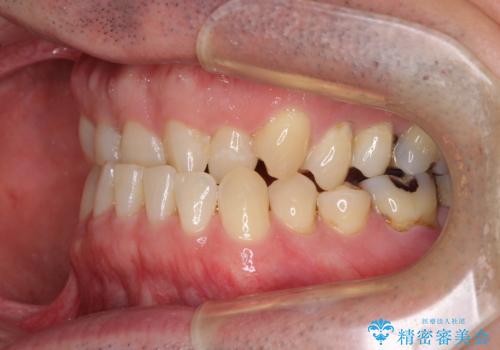

- 上下前歯の反対咬合と左下奥歯の痛みを気にして来院された患者様です。

歯並びや口元の印象、奥歯の咬み合わせから、非抜歯にて矯正治療を行うこととしました。

また、左下の奥歯は親知らずの影響で手前の歯の歯根までむし歯になってしまったため、親知らずとともに抜歯をし、インプラントによる補綴治療を行うこととしました。